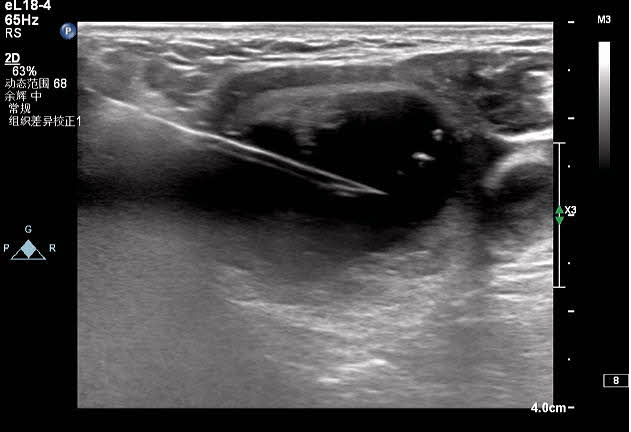

對結(jié)節(jié)的囊性部分進行穿刺抽吸+聚桂醇反復(fù)沖洗

對結(jié)節(jié)實性部分進行移動式+固定式射頻消融